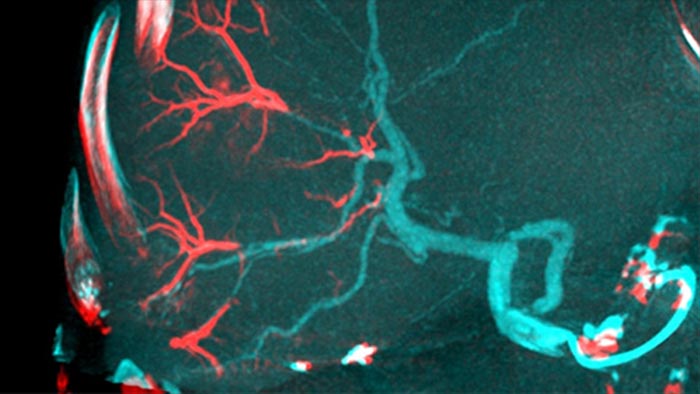

A CBCT Dupla permite a aquisição em 3D de uma fase arterial para visualizar estruturas vasculares e de uma fase pós-arterial (tardia) para visualizar o acúmulo do meio de contraste, em uma única etapa automática.5

O Dual View permite a visualização simultânea de dois conjuntos de dados da CBCT. Tanto a fase arterial quanto a fase tardia podem ser exibidas uma ao lado da outra ou em uma única exibição de sobreposição fundida.